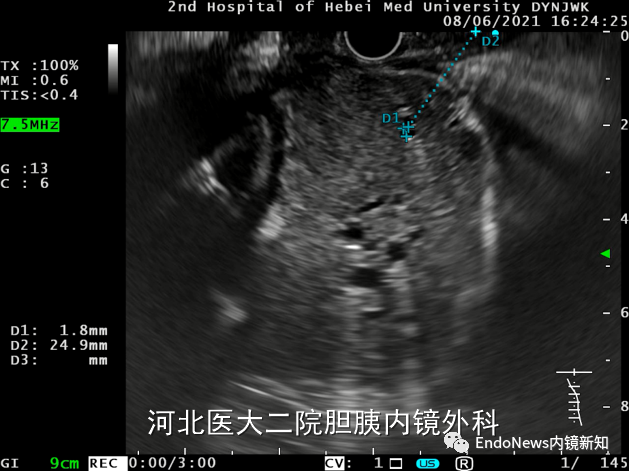

病例1患者的肝内胆管均比较细,操作难度比较高。对于这个病例,我们起初的方案是从S2段穿刺,这个位置距离比较近,但后来发现此位置的胆管才1.8mm,无法成功穿刺。

随后我们调整方法,试图从S3段穿刺,此位置胆管有2.7mm,但整个胆管扩张不是特别明显,并不是适合的位置,因此也放弃了S3段。